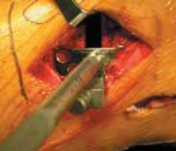

1. Proper bony anatomic landmarks are located.

1. The tibial tubercle, posteromedial tibia, and joint line are clearly identified with a skin marker.

2. The incision lies 2 to 3 cm posterior to the tibial tubercle and 1 cm distal to the joint line, and extends distally for 5 to 6 cm (

TECH FIG 2A

).

2. The incision is taken down through the skin and subcutaneous tissues, revealing the sartorius fascia (

TECH FIG 2B

1. The superior border of the gracilis hamstring tendon is palpated, and the sartorius fascia is opened along the superior border of the gracilis tendon.

2. Medially, the pes bursa is released from the medial tibial tubercle in an inverted L fashion.

3. The pes bursa is carefully elevated distally, taking great care to develop the plane between the bursa and the underlying medial collateral ligament.

4. Proximally, the retinaculum and layer 1 of the knee are incised to the approximate level of the joint line (

TECH FIG 2C